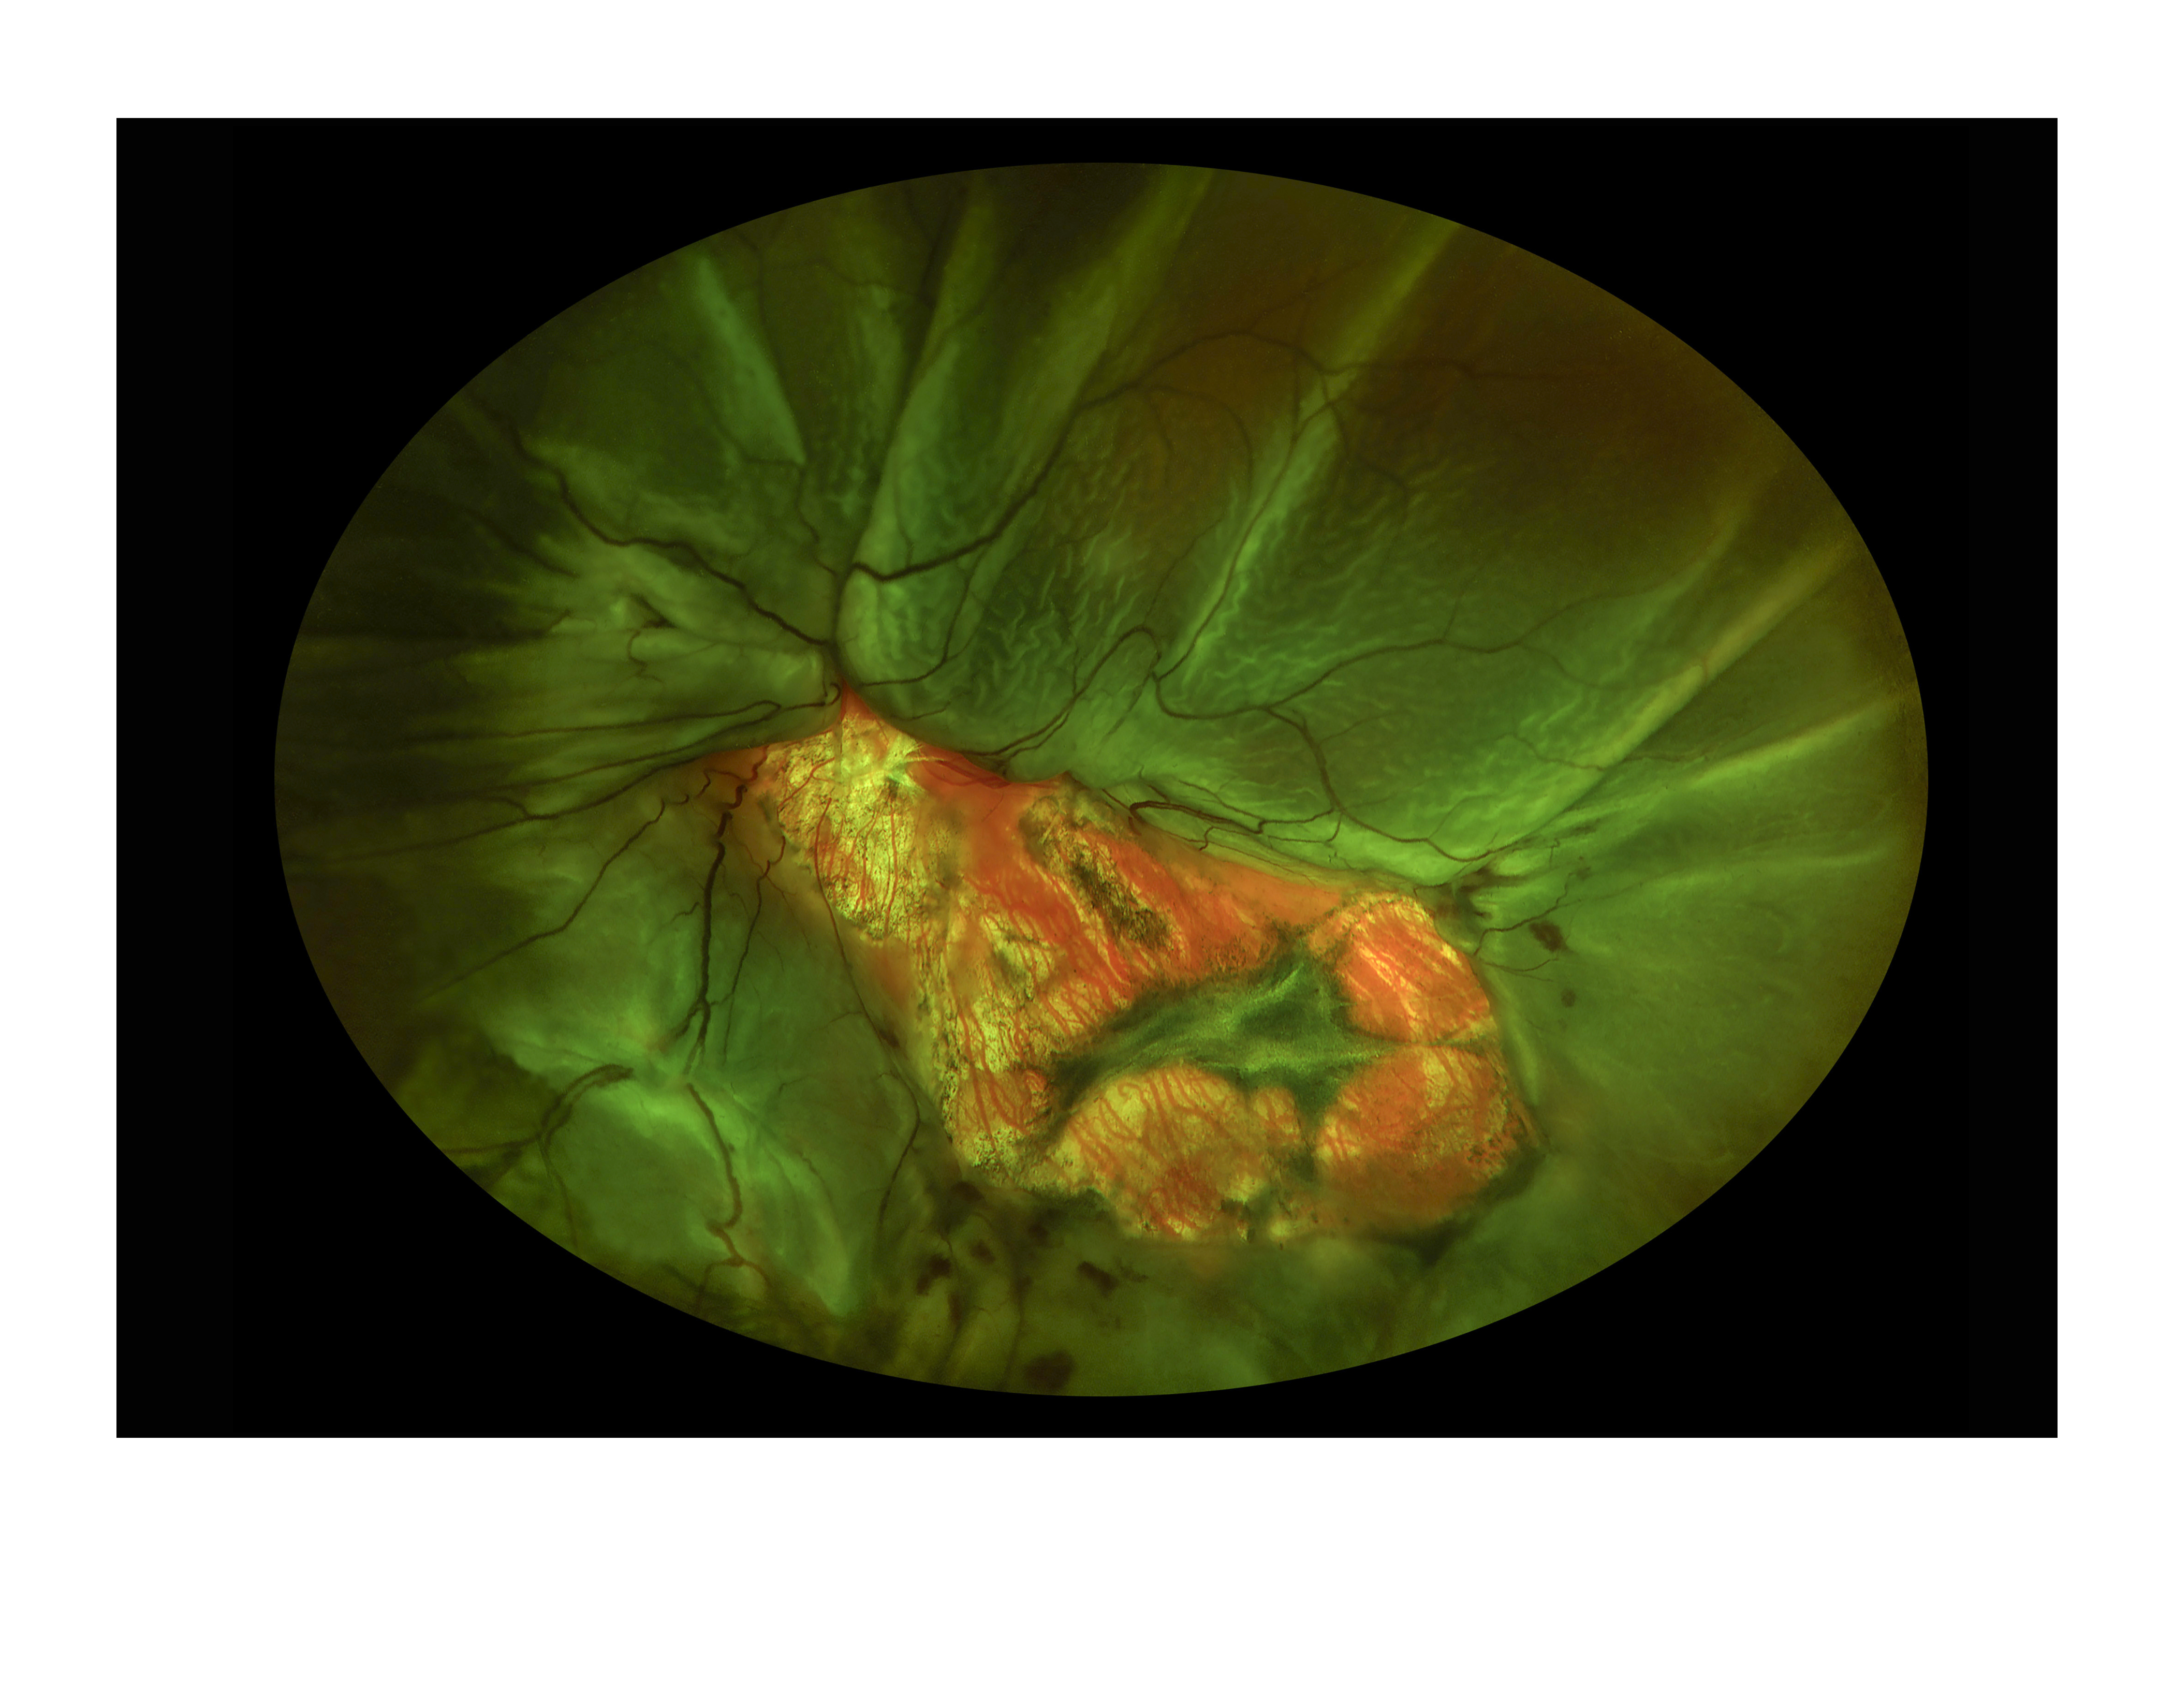

Funnel Detachment Presented by Judith Gulian, OCT-C This photograph received Second Place in the category "Ultra-Wide Field" and was displayed in the 2024 OPS Exhibit. Filed Under Retina OPS Photo